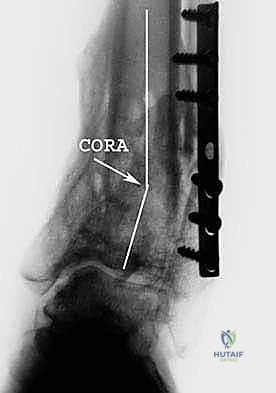

- الأشعة السينية الحاملة للوزن (Weight-bearing X-rays): وهي خطوة حاسمة. يجب أخذ صور الأشعة والمريض واقف، ليتمكن الدكتور هطيف من رسم المحاور الميكانيكية بدقة وحساب زاوية التشوه بالدرجات.

- التخطيط الرقمي: باستخدام برامج حاسوبية متقدمة، يقوم الدكتور هطيف بمحاكاة العملية الجراحية على الكمبيوتر قبل دخول غرفة العمليات، لتحديد حجم الإسفين المطلوب ومكان القطع بدقة مليمترية.

3. إجراء القطع العظمي (Osteotomy)

باستخدام أدوات قطع عظمية دقيقة جداً (مناشير جراحية متأرجحة)، وتحت توجيه جهاز الأشعة السينية المباشر في غرفة العمليات (C-arm)، يتم إحداث القطع في عظم الظنبوب في المكان المخطط له مسبقاً، مع الحفاظ على جزء بسيط من القشرة العظمية في الجهة المقابلة لتعمل كمفصلة (Hinge).

يتم فتح القطع العظمي بلطف وتدريجياً للوصول إلى الزاوية المصححة التي تم حسابها. هذه الخطوة هي جوهر العملية، حيث يتم استعادة المحور الميكانيكي السليم للساق.